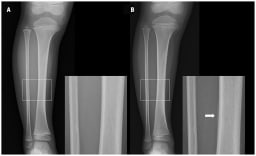

Ein 39-jähriger Mann stellte sich mit Schmerzen im linken Unterarm in der Notaufnahme vor, nachdem er bei einem Motorradunfall gestürzt und mit ausgestreckter, pronierter Hand auf dem Boden aufgeschlagen war.

Abb.1 A) Anteroposteriore bzw. B) laterale Röntgenaufnahme des linken Unterarms

© Tsai YY & HC Shen. CMAJ 2025; 197(34): E1113